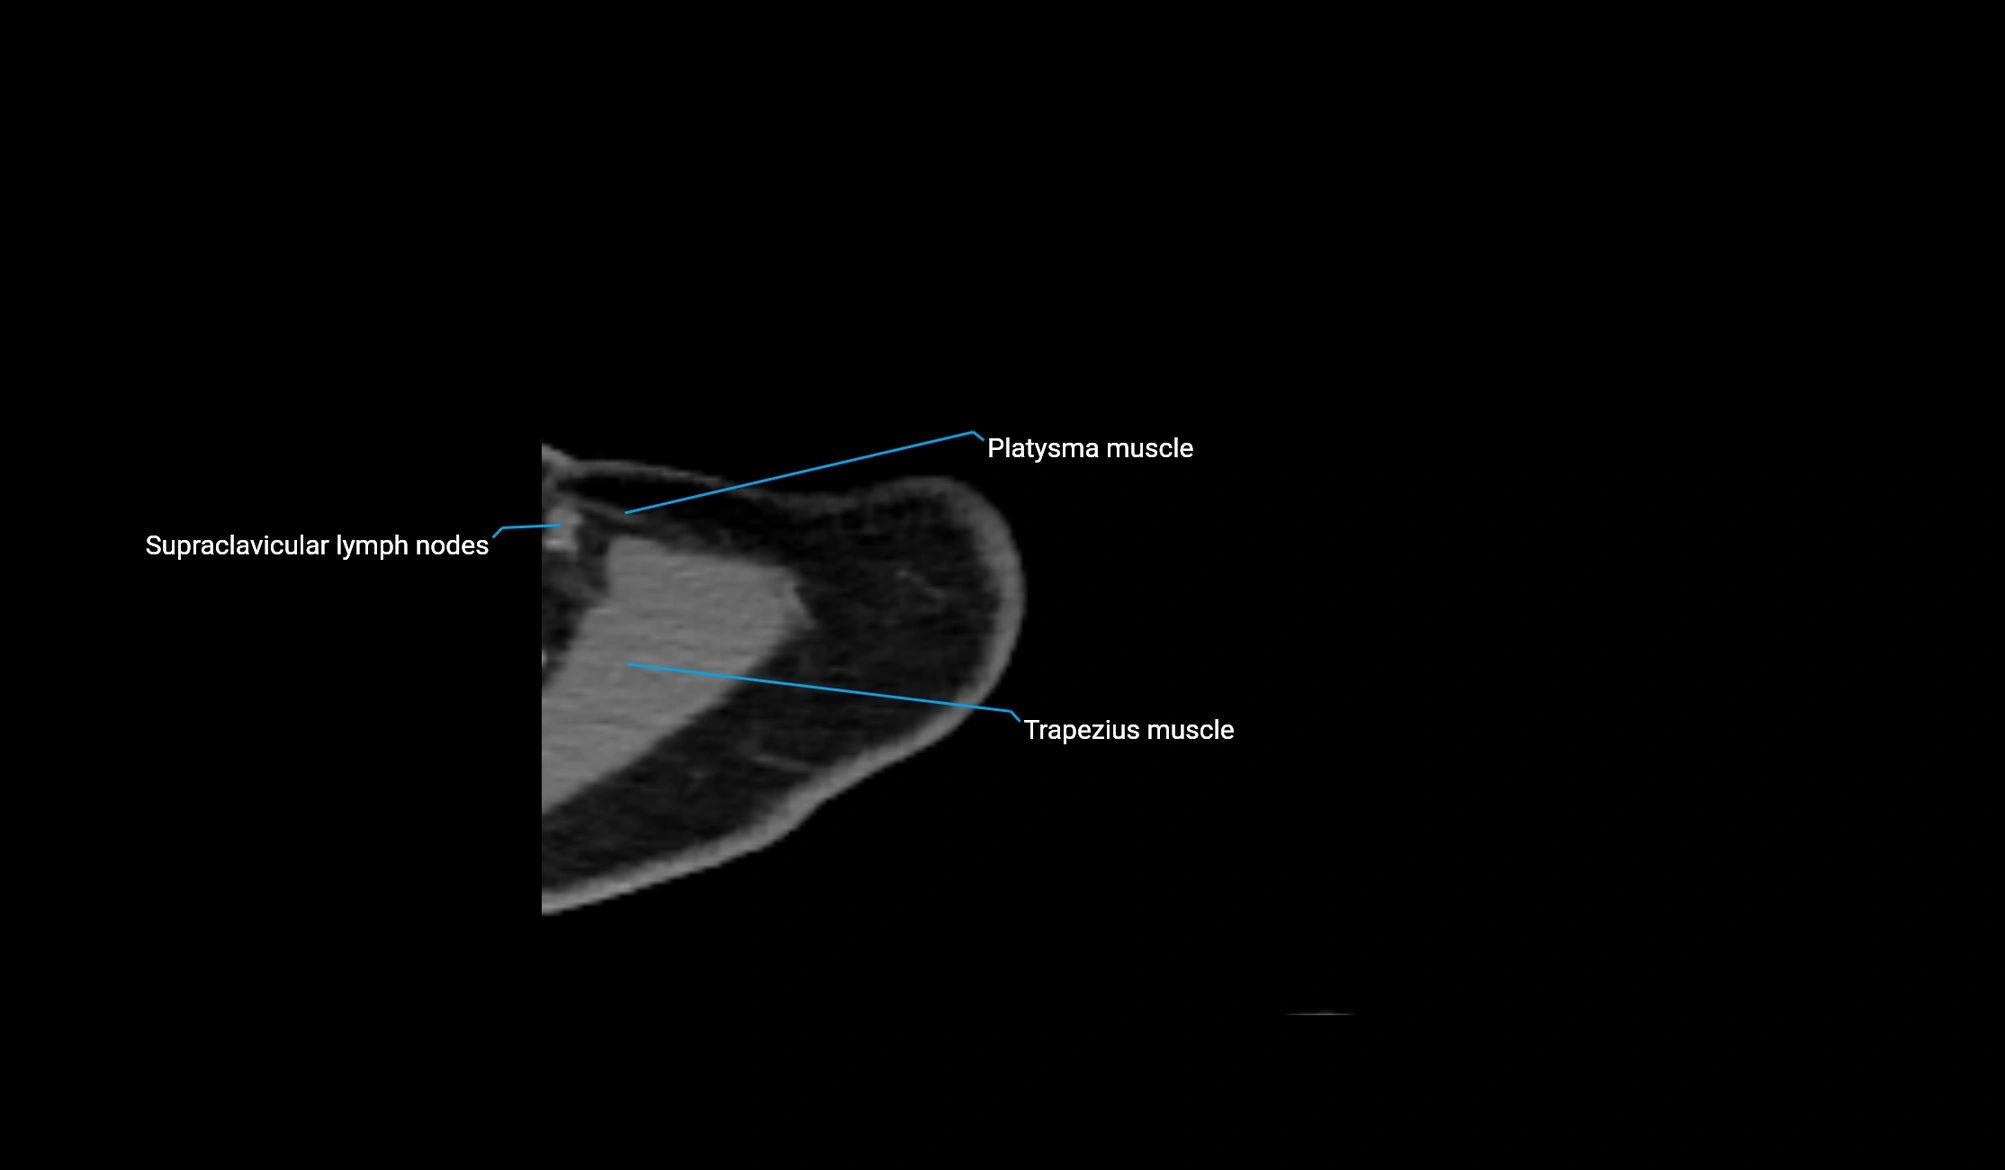

MRI image